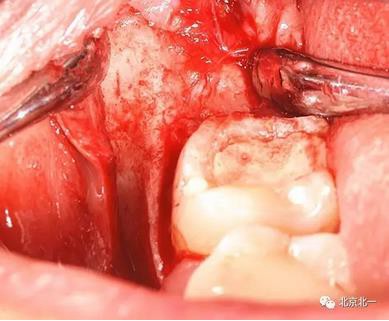

圖七:去骨后看不見牙齒位置方向。顏色無法區分,拍片確認一下剛才去骨的以及截的冠就是智齒。

圖八:把牙根優先取出后還是看不見牙冠在哪里,實在貼的神經管太近, 只能再次拍一個cbct確認。